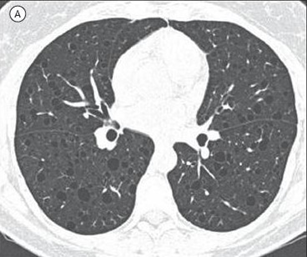

A imagem tomográfica mais frequentemente associada à linfangioleiomiomatose é a seguinte: